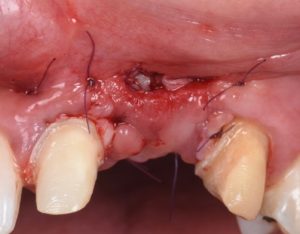

The procedure demonstrates the use of a horizontal vestibular incision with tunneling to mobilize the soft tissues and elevate the papillae. An autogenous connective tissue graft (CTG) harvested from the palate and maxillary tuberosity is utilized to augment tissue thickness. Additionally, a xenogenic bone graft is placed over the crestal area to serve as a space-maintaining scaffold and support vertical tissue stability.

Advanced flap advancement and suturing techniques are highlighted to ensure graft stability and optimal soft tissue outcomes.